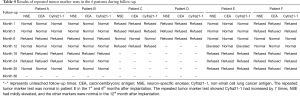

The patients were followed up 1, 3, 6, 12, 18, 24, 30 and 36 months after procedure. The follow-up is displayed in Table 2.

Full table

No nausea, vomiting, headache or dizziness occurred in any of the patients after implantation. The completed blood cell test showed no bone marrow suppression. The clinical symptoms were significantly relieved in all the patients. During follow-up, recurrence of primary lesion and left lung metastasis occurred in patient E in the 12th month after procedure, recurrence of primary lesion occurred in patient F in the 36th after procedure, while no recurrence or metastasis occurred in the other patients. No patient had distant metastasis during follow-up. No radiation pneumonia, radiation esophagitis, esophago-tracheal fistula, particle drop-off, migration or other serious complications occurred. The results of repeated tumor marker tests in the 6 patients during follow-up are visible in Table 4.

Full table